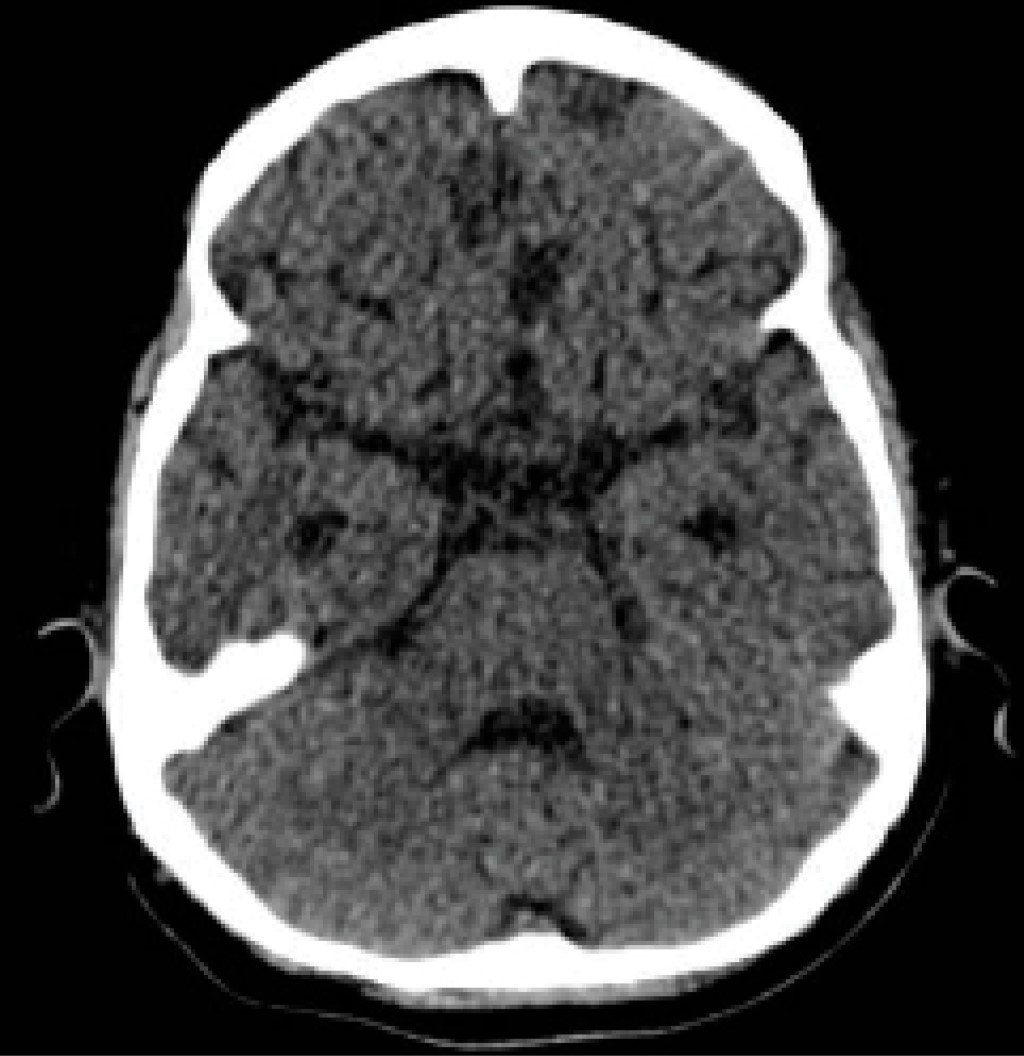

Los estudios de laboratorio muestran los siguientes resultados positivos ANA ++, C4 < 6.35 (15-45), C3 53.6 (83-177), anti-La 139.85, anti-Ro 194, proteinuria (6 g en 24 horas) (en la Tabla 1 se resumen los estudios de laboratorio a su ingreso) y se integra diagnóstico de lupus eritematoso sistémico de acuerdo a la Alianza Europea de Asociaciones de Reumatología (EULAR, por sus siglas en inglés) con criterio de entrada ANA ++ y 12 puntos de criterios adicionales, proteinuria (3 puntos), hipocomplementemia (4 puntos) y crisis convulsivas (5 puntos), iniciando manejo con metilprednisolona a 1 mg/kg/día, ciclosporina a 2 mg/kg/día y gammaglobulina a dosis inmunomoduladora 2 g/kg/dosis, dado que en ese momento se encontraba con infección activa. Presenta deterioro a nivel neurológico (crisis convulsivas), por lo que se inicia rituximab 4 dosis semanales a 375 mgm2SC y se administran cuatro pulsos de metilprednisolona 30 mg/kg/dosis (Figura 3).

Posteriormente presenta hipertensión arterial sistémica y síndrome de encefalopatía posterior reversible (PRES) (Figura 4), por lo que se suspende ciclosporina y se inicia ácido micofenólico. Se comienza manejo con amlodipino, enalapril y alfametildopa logrando control de tensión arterial. Tras persistir con hipocomplementemia, proteinuria, alteración neurológica y linfopenia prolongada, se le administra ciclofosfamida 2 mg/kg/día, sin embargo, presenta citopenias por lo que se suspende a la semana de inicio. La paciente fue operada de funduplicatura, gastrostomía laparoscópica y traqueostomía, sin eventualidades.

Figura 4